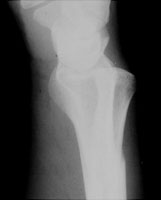

- Click on the image for a larger versionALateral radiograph of the wrist. This shows radioulnar dislocation.